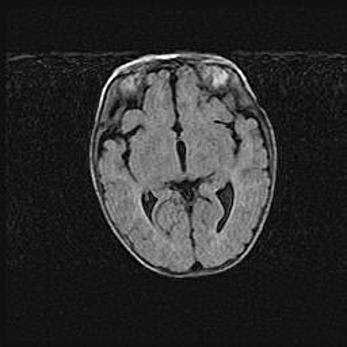

Церебральная ишемия II.

Возраст: 5 дней

Вес: 3400 г

Пол: женский

Окружность головы: 35 см

Срок гестации: 39 недель

Церебральная ишемия – это заболевание, характеризующееся недостаточностью (гипоксией) либо полным прекращением (аноксией) снабжения мозга кислородом по причине закупорки одного или нескольких сосудов. Это приводит к  что метаболическим расстройствам различной степени тяжести в тканях головного мозга, развитию коагуляционных некрозов и гибели нейронов.